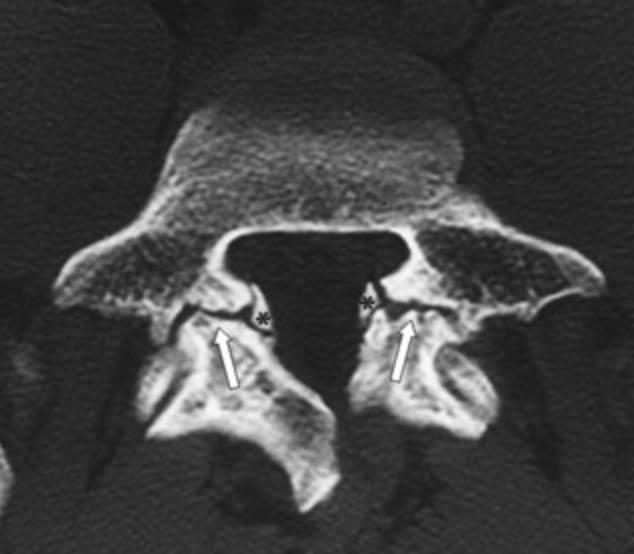

2. Espondilolisis

¿Qué es la Espondilolisis?

Se trata de una fractura en el istmo de la vertebra que es la zona que une la parte anterior con la posterior de la vertebra, no son congénitas (no se nace con ellas), si no que aparecen con el desarrollo (Fig 2).

¿Por qué se produce la espondilólisis?

Hay razas con cierta predisposición genética, como pueden ser los esquimales (un 45-55 % la padecen sin repercusión funcional). En nuestro medio sobre todo se producen como lesiones de estrés, con un cizallamiento de la pars interarticularis como consecuencia del movimiento repetitivo en extensión de la columna lumbar.

¿Cómo se diagnostican?

El diagnóstico es habitualmente clínico cuando los niños nos cuentan que tienen dolor en relación con la actividad deportiva y que mejoran en reposo.

La radiografía simple es la primera prueba diagnóstica ya que en proyecciones oblicuas podemos intuir o confirmar mejor este diagnóstico. En ocasiones es necesario realizar una RM o un TAC. Si existen dudas diagnósticas se puede completar el estudio con una gammagrafía ósea que consiste en la inyección de isotopo radiactivo que se deposita en los lugares en los que hay una actividad inflamatoria aumentada y nos marca el lugar de la lesión.